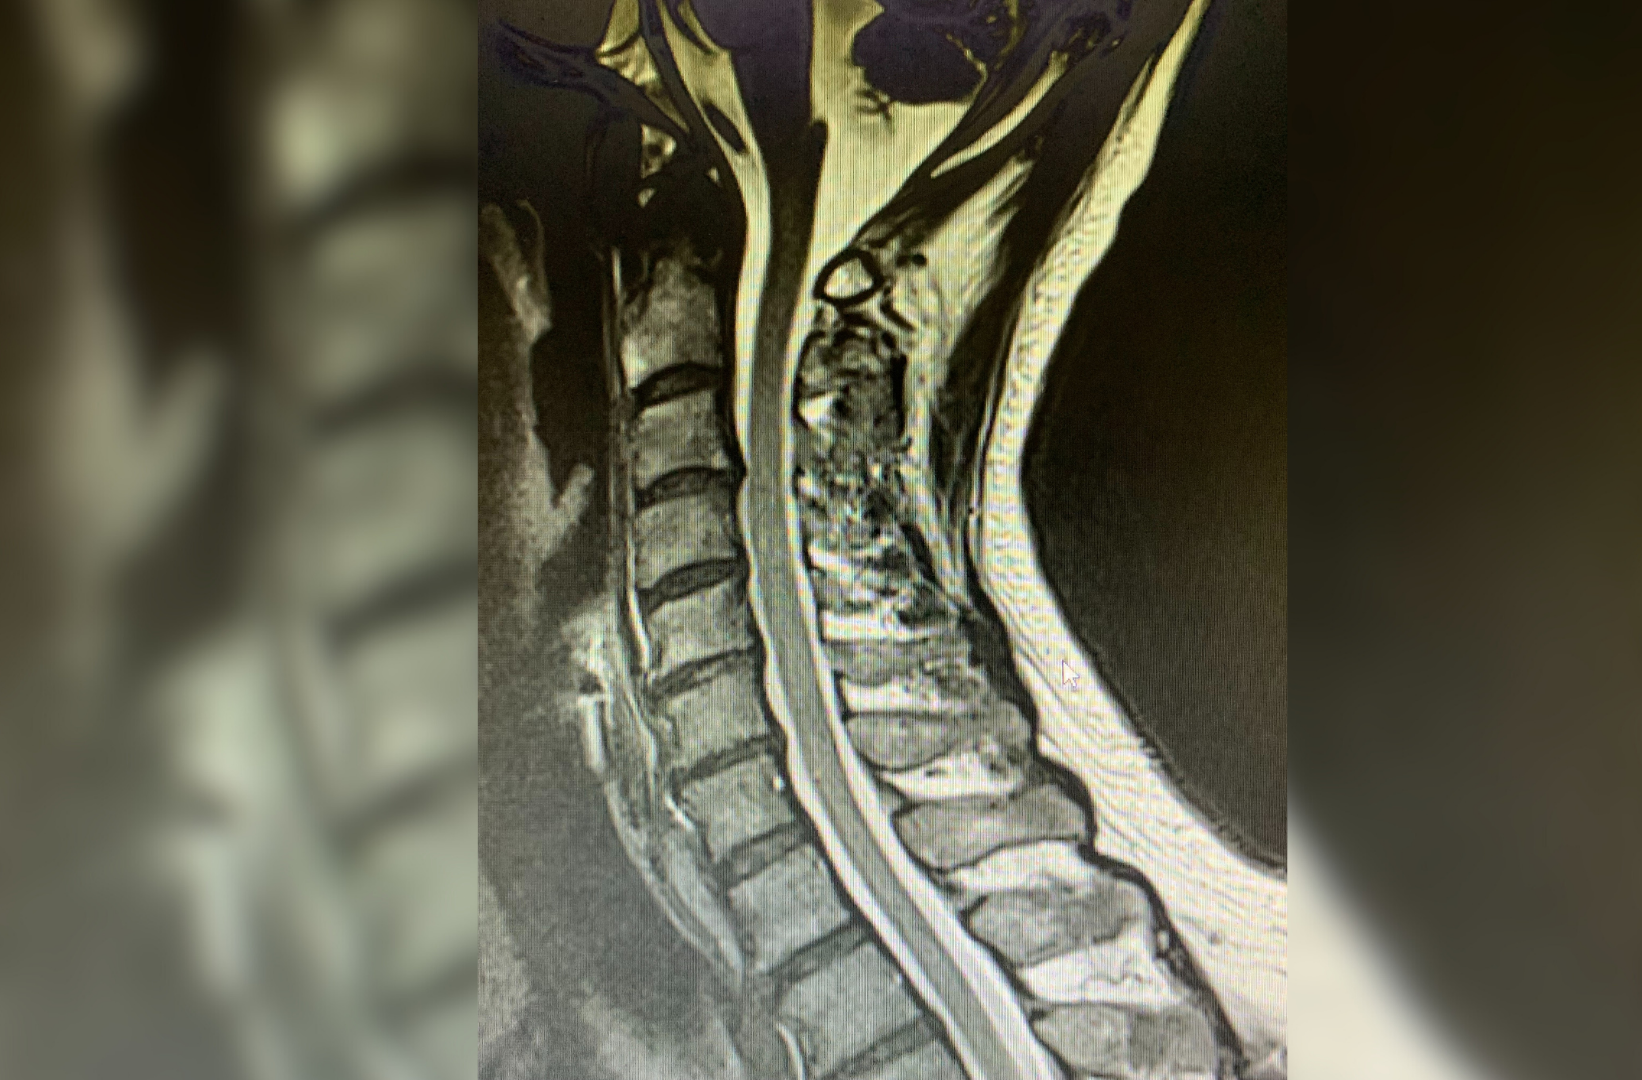

At CSDC, Dr. Chong focuses on comprehensive spine consultations and providing tailored treatment plans, leading to effective results for people suffering from chronic back pain and neck pain, degenerative, bulging, and herniated discs often with severe low back pain, sciatic pain, or pinched nerves. He utilizes his many years of practice, to carefully assess and analyze patient X-rays, MRI’s, and related clinic results via NETCARE, assisting him to provide patients with an accurate working diagnosis during each spine consultation.

We offer both Cervical and Lumbar spine decompression.